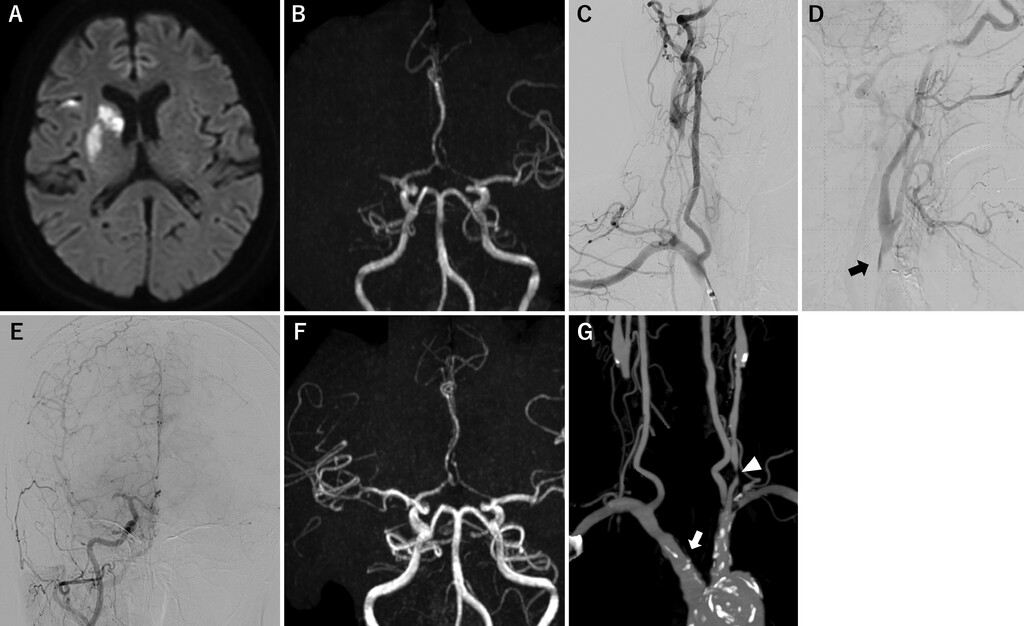

FIG. 1. Images obtained at the onset of right middle cerebral artery occlusion. A: MR diffusion-weighted image at onset. A high signal intensity was observed in the right caudate nucleus, basal ganglia, and cerebral cortex. B: MR angiogram at onset. Occlusion of the proximal right middle cerebral artery was observed. C: Right brachiocephalic artery angiogram showing occlusion from the origin of the right CCA. D: Right brachiocephalic artery angiogram (equilibrium phase). Contrast stagnation is observed at the blind end of the right CCA (arrow). E: Right brachiocephalic artery angiogram revealing occlusion of the right middle cerebral artery. F: MR angiogram obtained 3 days after onset, revealing recanalization of the right middle cerebral artery. G: Cervical CT angiogram showing occlusion of the right CCA (arrow) and severe stenosis of the left CCA (arrowhead).